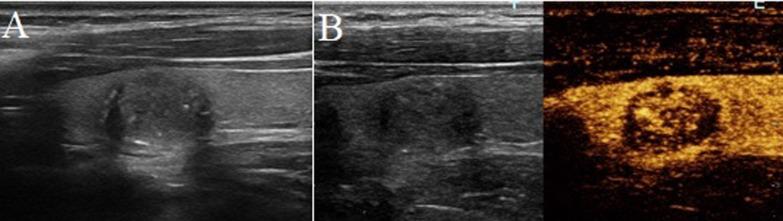

Seventy-four consecutive thyroid nodules with halo sign on B-mode ultrasound were pathologically confirmed by surgery or fine needle aspiration, including 43 benign and 31 malignant lesions. All these lesions underwent pre-operative CEUS examination. The CEUS features, including enhanced time, enhanced intensity and homogeneity, and presence of enhancing ring, were compared between benign and malignant ones.

Enhanced intensity was significant different between benign and malignant lesions with halo. Hypo-enhancement was more frequently detected in malignant nodules than that in benign ones, compared with iso-enhancement and hyper-enhancement (p = 0.013, and = 0.014, respectively). Detection rate of high-enhancing ring was significantly higher in benign nodules than that in malignant group (p = 0.001). While in nodules > 10 mm, only high-enhancing ring was the distinguishing feature between benign and malignant nodules.

Enhanced intensity and high-enhancing ring may be helpful in the differential diagnosis of thyroid nodules with halo sign on B-mode ultrasound.